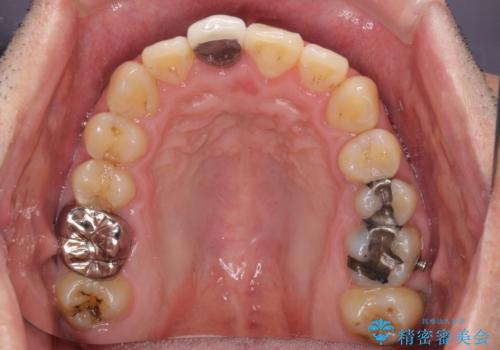

- 前歯のデコボコと上下のクロスバイトを気にして来院された患者様です。

インビザラインを用い、IPR(歯と歯の間を削る)と歯列全体を拡大させることで、歯並びを整えていくこととしました。

上の前歯が下の前歯を乗り越える際、奥歯がほとんど咬めない時期があり、乗り越えた後も、インビザライン特有の奥歯の咬みにくさが続きました。

咬み合わせ改善のために治療期間を要しましたが、最終的に奥歯はしっかりと咬めるようになりました